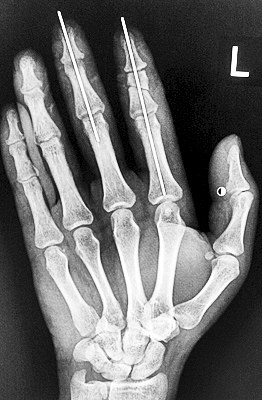

術后X光顯示,骨骼對位良好。

最終,盧微波和團隊找好了需要的血管和神經,做好標記后,開始固定食指骨骼、吻合肌腱,最后在顯微鏡下用直徑20微米的無創(chuàng)顯微縫合線開始吻合血管和神經。

在經過兩個多小時手術后,早上8時許,盧微波下令松止血帶,數(shù)十秒后男子蒼白的食指逐漸紅潤起來,食指在離體10個小時后恢復血運。

緊接著,盧微波又開始中指再植手術。上午10時許,中指在離體12小時后也成功恢復血運。